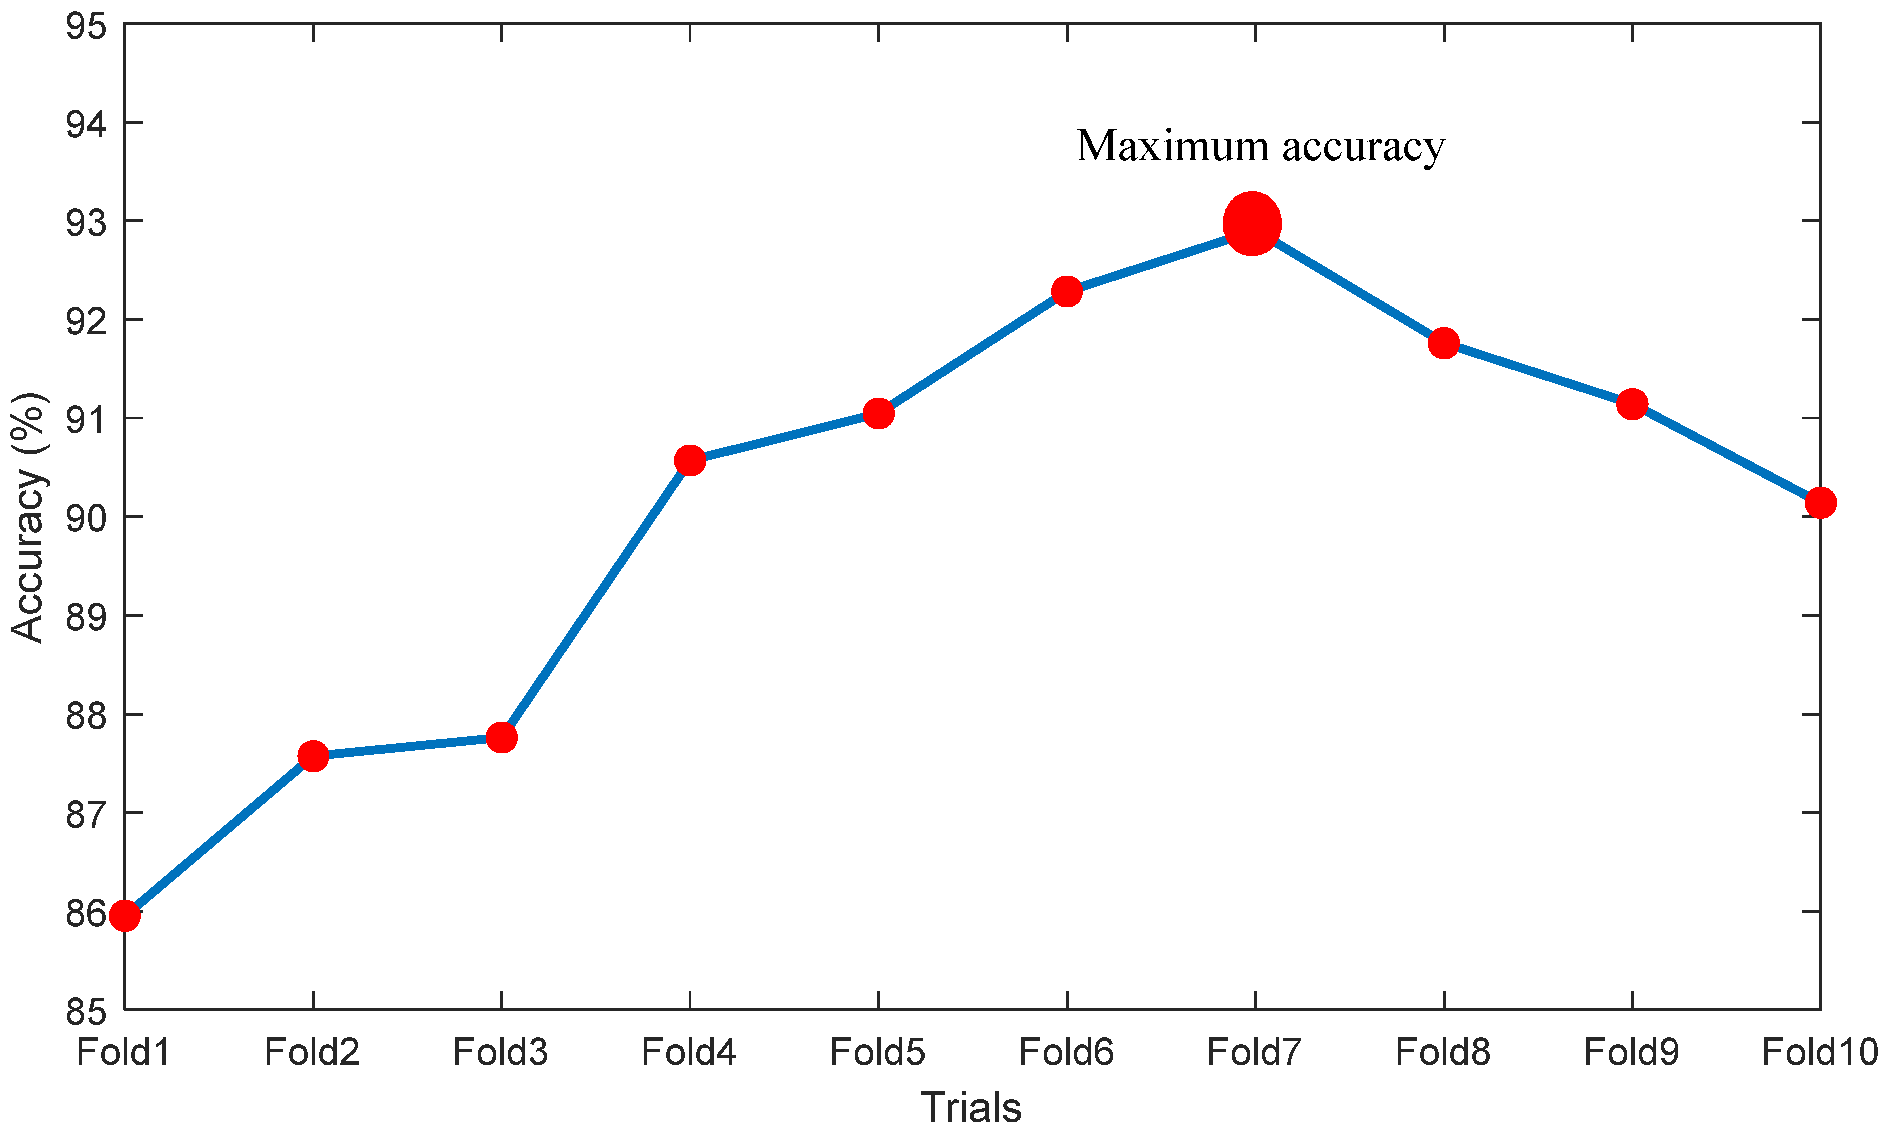

| Trials | TP | FN | TN | FP | ACC% | PRE% | SEN% | SPE% | NPV% |

|---|---|---|---|---|---|---|---|---|---|

| Fold1 | 892 | 158 | 913 | 137 | 85.9524 | 86.6861 | 84.9524 | 86.9524 | 85.2474 |

| Fold2 | 907 | 143 | 932 | 118 | 87.5714 | 88.4878 | 86.3810 | 88.7619 | 86.6977 |

| Fold3 | 904 | 146 | 939 | 111 | 87.7619 | 89.0640 | 86.0952 | 89.4286 | 86.5438 |

| Fold4 | 958 | 92 | 994 | 106 | 90.5714 | 90.0376 | 91.2381 | 89.9048 | 91.1197 |

| Fold5 | 964 | 86 | 948 | 102 | 91.0476 | 90.4315 | 91.8095 | 90.2857 | 91.6828 |

| Fold6 | 973 | 77 | 965 | 85 | 92.2857 | 91.9660 | 92.6667 | 91.9048 | 92.6104 |

| Fold7 | 979 | 71 | 972 | 78 | 92.9048 | 92.6206 | 93.2381 | 92.5714 | 93.1927 |

| Fold8 | 961 | 89 | 966 | 84 | 91.7619 | 91.9617 | 91.5238 | 92.0000 | 91.5640 |

| Fold9 | 954 | 96 | 960 | 90 | 91.1429 | 91.3793 | 90.8571 | 91.4286 | 90.9091 |

| Fold10 | 942 | 108 | 951 | 99 | 90.1429 | 90.4899 | 89.7143 | 90.5714 | 89.8017 |